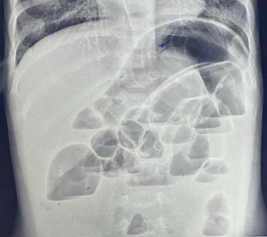

In paralytic ileus, there is too much gas in both small and large bowels (Figure 4 & 5).

Figure 4 Anteroposterior supine abdominal radiograph in a 4-year-old child showing multiple dilatated bowel loops scattered throughout the abdomen haphazardly with presence of gas in the rectum suggestive of paralytic ileus.

Figure 5 Anteroposterior supine abdominal radiograph in a 9-month-old infant with abdominal distention following diarrhea showing dilatated bowel loops with smooth walls scattered throughout the abdomen haphazardly with presence of gas in the rectum suggestive of paralytic ileus.